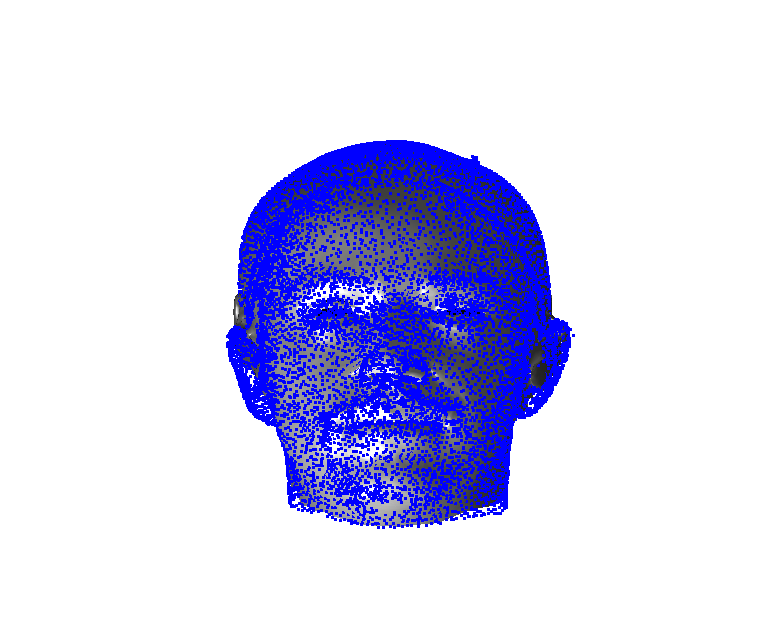

Toolsets to define normal appearance and therefore both assist with planning of surgery and define optimal outcomes from a range of surgical interventions are currently either crude or lacking. Therefore, the unit collected a large, high quality 3D image dataset of 1523 human heads. An example is given in Fig. 1 showing the 3D channel only on the left, and the 3D data with texture pasted on on the right. The data was collected over well-conserved demographics, and an age range of 1 to 89 years, see Fig. 2. The dataset was collected with the aim of developing a normal equivalent of the human cranium and face in order develop the tools to enhance patient experience following surgery. We plan to make the dataset publicly available in the near future.

Our system can accept 3D images in arbitrary pose and employs an automatic landmarking scheme to normalise the pose of the 3D head before any further processing. Two examples of typically varying initial pose taken from the headspace datset are shown in Fig. 4.

Fig. 9 shows examples of the fitted model (trained on FRGC data) on the first four subjects in our Headspace training set. Note that the mean of the landmarks in the sparse model is centred on the orgin, and so the scan data is moved towards that and becomes frontal in pose. We note that other researchers [28] have used 3D landmark localisation to find the head, but often this only includes landmarks that are relatively easy to localise, namely inner eye corners and nose. Localising more landmarks over a wider facial area has a number of advantage in terms of cropping, pose normalisation and global 3D template warping, all of which are described later.